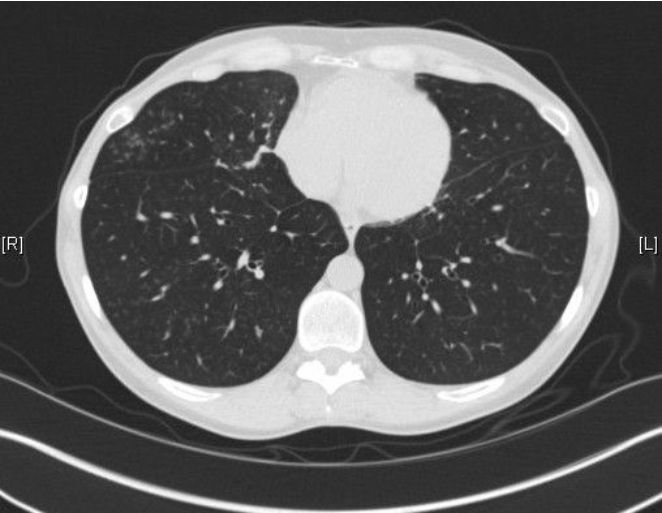

Beyond plain sections of tissue on a slide, there are many ways to observe pathology: fluorescent staining (FISH), staining for various microbial organisms, electron microscopy to delineate finer details, as well as other methods such as radiologic exams (CT scans, PET scans, etc.) These images can be striking for two very different reasons: they can diagnose a very serious disease such as cancer, and they can be aesthetically beautiful.

In Hidden Beauty: Exploring the Aesthetics of Medical Science, a large collection of beautiful albeit pathological images are compiled to serve as both art and education. As one of the authors, pathologist Dr. Iacabuzio-Donahue, points out, most people better understand concepts when they are presented visually. A complex disease can be explained by pictures and diagrams. I find that drawing even rough representations for patients allows them to have a clearer understanding of what is going on. Showing them a CT scan of their lungs damaged by COPD is far more poignant than explaining in words what smoking does to the lungs. Likewise, showing people how the normal becomes abnormal as seen under a microscope can be very useful.